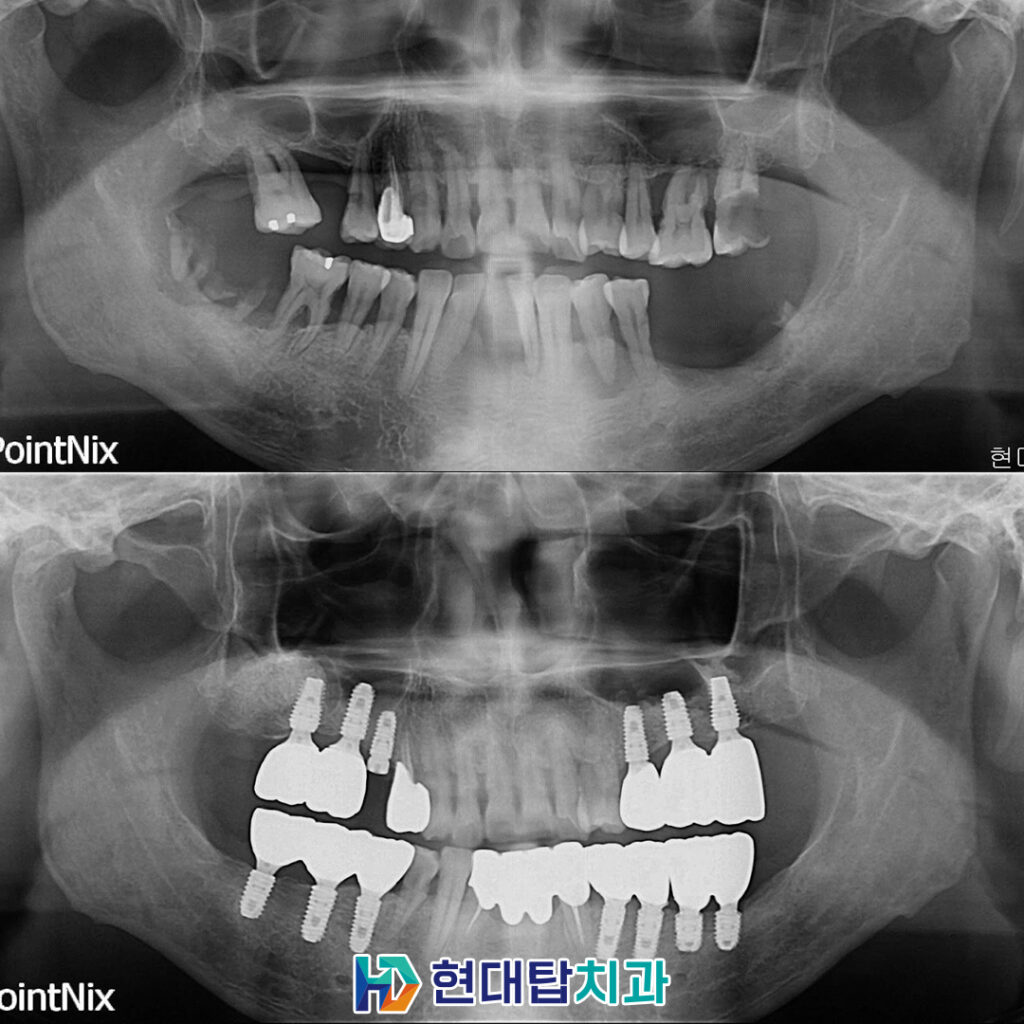

본 환자분은 50세 남성 환자분으로

본원에 내원 중이신 환자분의 소개로

내원해 주셨습니다.

전체적으로 잇몸뼈의 소실이 크셨고

아래 앞니는 많이 흔들려서 저절로

발치가 된 상태로

전반적인 치아의 상실과

충치, 치주 질환, 잇몸 염증으로 인해

잇몸뼈의 상태가 많이 좋지 않으셨습니다.

처음 내원해 주셨을 때 촬영한

구강 내 사진입니다.

치아를 상실한 부위

뼈이식을 동반한 임플란트와

까맣게 뿌리만 남아있는 부분은

발치 후 임플란트를 진행하기로 하였습니다.

또한 아래 앞니는 예후가 좋지 않은

치아 발치 후 4개의 브릿지로

연결하여 사용하시기로 하였고

크고 작은 충치들은 레진과

보철치료로 계획을 수립하였습니다.

최종 보철까지 완성된 모습입니다.